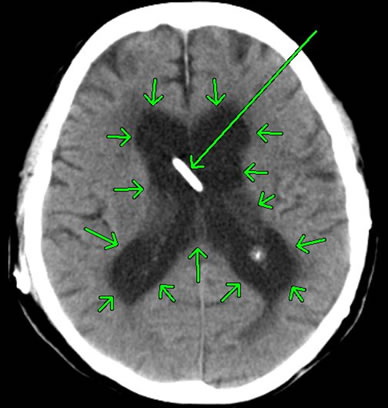

それでは、外傷性脳室出血の画像を見てみましょう。

中央部に、白く細長い像が見えます。これは「脳室内出血を抜き取るドレーンチューブ」です。